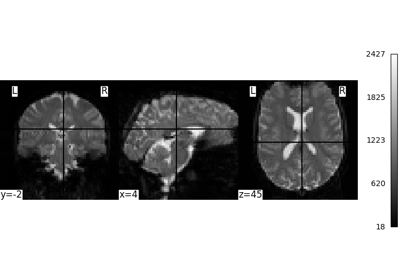

Compute the mean EPI for one individual of the brain development

dataset downloaded with nilearn.datasets.fetch_development_fmri and

smooth it with an FWHM varying from 0mm to 20mm in increments of 5mm

Intermediate steps:

Run

nilearn.datasets.fetch_development_fmriand inspect the.keys()of the returned objectCheck the

nilearn.imagemodule in the documentation to find a function to compute the mean of a 4D imageCheck the

nilearn.imagemodule again to find a function which smoothes imagesPlot the computed image for each smoothing value